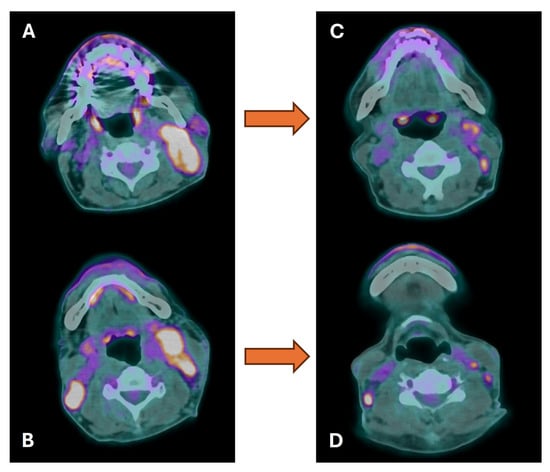

4. Radiotherapy Planning

- Thureau, S.; Briens, A.; Decazes, P.; Castelli, J.; Barateau, A.; Garcia, R.; Thariat, J.; de Crevoisier, R. PET and MRI guided adaptive radiotherapy: Rational, feasibility and benefit. Cancer Radiother. 2020, 24, 635–644. [Google Scholar] [CrossRef]

| Adaptive radiotherapy | Escalation or de-escalation during treatment |